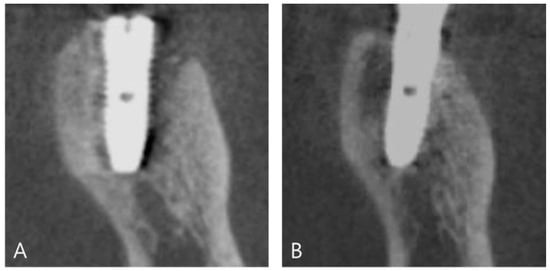

2. Materials and Methods

2.2. Surgical Procedure (Application of a DDB)

3. Results